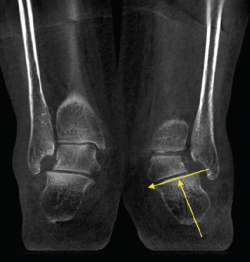

Figura 2. Severo pie plano valgo bilateral con pinzamiento fibular.

- Pie plano valgo del adulto. Permite la valoración de la articulación subtalar, el valgo del retropié y la inestabilidad de la columna medial (Figuras 2 y 3).